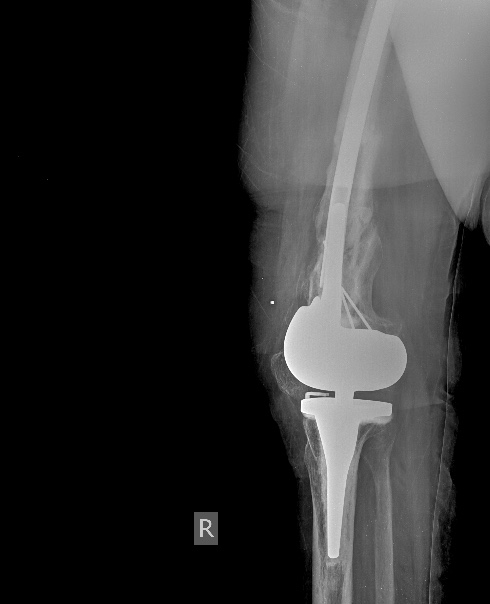

Все прошло по плану. Длину восстановили дистрактором. Пришлось сделать небольшую чрескожную остеотомию, чтобы устранить смещение по ширине.

Обратила на себя внимание наружная ротация стопы по отношению к колену. И получилось ее устранить с небольшим усилием. То есть присутствует еще и нестабильность большеберцового компонента. Есть ли какие-то мысли, как ее устранить, не меняя эндопротез?

Боковая проекция оперированной конечности.